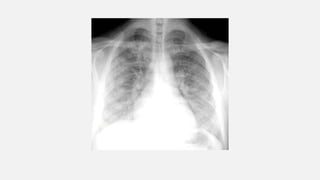

• #27 Perihilar “bat-wing” consolidation in pulmonary edema. A: Chest radiograph shows a distinct perihilar predominance of consolidation. The heart is enlarged. B: CT shows sparing of the lung periphery.